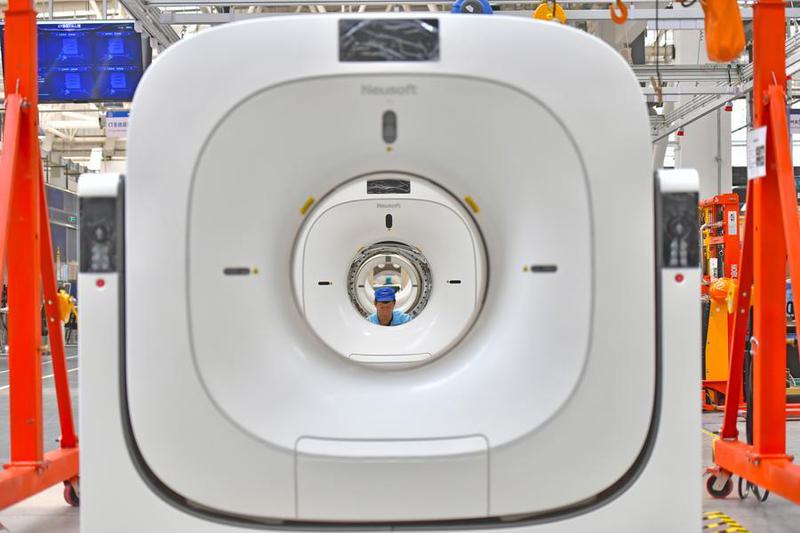

Los productos tradicionales de alto rendimiento del país, como los ingredientes farmacéuticos químicos activos y los dispositivos médicos, han mantenido una importante participación en el mercado mundial, mientras que su volumen de exportación ha aumentado de forma constante, detalló el ministerio.

Las exportaciones chinas de productos farmacéuticos y dispositivos médicos avanzan constantemente hacia sectores de mayor valor añadido, con los medicamentos innovadores, las formulaciones de alta gama y los dispositivos médicos de alto rendimiento como prioridad, de acuerdo con funcionarios que asistieron a una conferencia organizada el sábado en Beijing por la Administración Nacional de Seguridad Sanitaria.